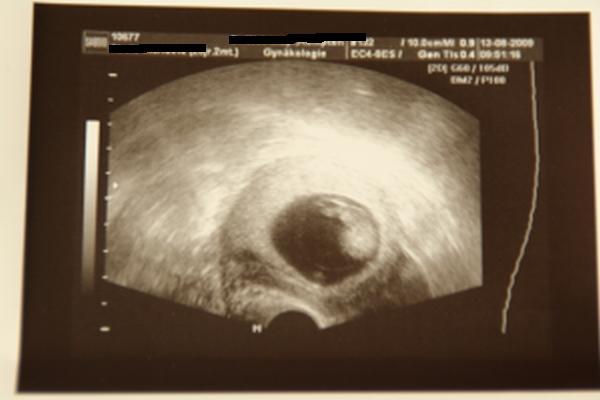

ist meine 1. SS und ich war einfach zu beunruhigt, als dass ich noch 2 Wochen auf den nächsten Termin warten konnte... Das Stechen im Eierstock ist normal, weil das Kind von dort versorgt wird, heißt, das HCG wird dort gebildet, bei mir im Linken, weil dort das reife Ei gesprungen ist. Ein Gutes hats auch noch, hab ein neues Bildchen bekommen, Baby ist 2,3 cm groß, zeitgerecht entwickelt und es hat geschlafen, sooo süß. Bild anbei. lg Manu, die überglücklich ist

Bild zu War doch beim Doc.... - Forum für März - Mamis